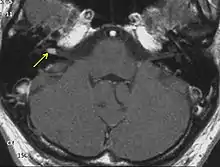

Although a Gadolinium enhanced magnetic resonance imaging (MRI) scan is the best method to confirm a vestibular schannoma, other methods of examination may arouse suspicion of a vestibular schwannoma.

Advances in scanning and testing have made possible the identification of small acoustic neuromas (those still confined to the internal auditory canal). MRI using Gadolinium as an enhancing contrast material is the preferred diagnostic test for identifying acoustic neuromas. The image formed clearly defines an acoustic neuroma if it is present and this technique can identify tumors measuring down to 5 mm (0.2 in) in diameter (the scan spacing).